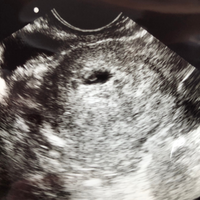

胎嚢は、早ければ「妊娠4週後半」から確認できるようになります。 なお、妊娠4週は、妊娠していない場合の生理予定日の週です。 超音波検査の画像で見ると、胎嚢は「黒い円」のような形で、「周囲に白い縁取り(=絨毛膜)」があります。 妊娠5週前半になると、胎嚢の中にリング状 こんちには!こんばんは!おはようございます! ちぬマロ🌰です。 前回5回目の体外受精によってはじめて妊娠判定が出ました! 次のステップである胎嚢確認ですが、昨日おにぎり🍙ちゃん(妻)が検査に行ってきたので、報告します! 妊娠5週目胎嚢確認? 6週目で胎嚢しか見えないことについて person 40代/女性 解決済み エコーの結果では 5週2日 胎嚢95mmのみ 確認 6週 1日 胎嚢165mm のみ確認 で、心拍や胎芽、卵黄嚢は確認できませんでした。 5週2日の時点で先生はこの時期に卵黄嚢が見えても良い

妊娠5週初期では、まだ超音波検査の画像では赤ちゃん(胎芽)が見えていないことが多いです。 妊娠5週後半になると、赤ちゃんが見え始めてきます。 妊娠6週の⼤きさ 胎嚢は15cmほどになり、胎嚢の中の白っぽい円も大きくはっきりと見えるようになり 7週で胎芽見えず&不育症検査すべきか 現在妊娠7週2日の妊婦です。 自然妊娠ですが、生理周期は26日ときっちり、予定される排卵日前に1回だけしか性交してないことから週数にズレはあまりないと思います。 先週、6週2日に初診でいったら、12ミリの胎嚢